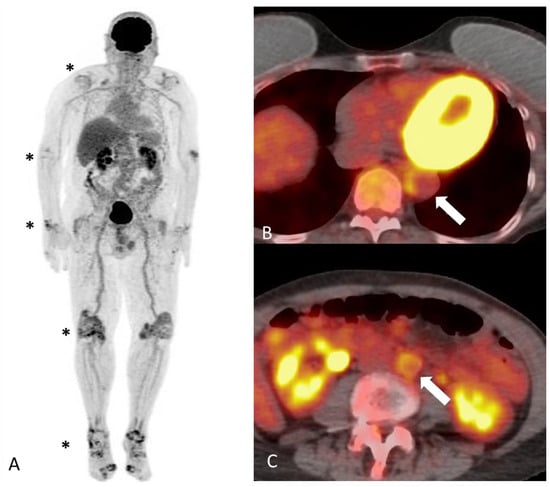

- Chen, Z.; Zhao, Y.; Wang, Q.; Li, Y.; Li, H.; Zhou, Y. Imaging features of 18F-FDG PET/CT in different types of systemic vasculitis. Clin. Rheumatol. 2022, 41, 1499–1509. [Google Scholar] [CrossRef] [PubMed]